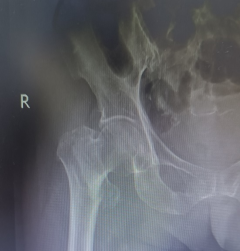

今年8月,88岁的胡奶奶不慎跌倒,被紧急送往就近医院救治。检查结果令人揪心:右侧粗隆间骨折!同时伴有2型糖尿病合并酮症酸中毒、心功能不全、肺部感染,肾功能不全等多重疾病。由就近医院进行风险评估后,建议转院治疗,最终家属经过多方打听,抱着一线希望来到南昌市人民医院。

左图为X光 股骨粗隆间骨折;术后内固定术后